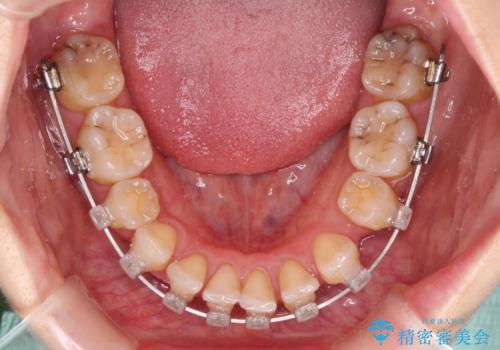

- クリアブラケット

骨格的な左右差と、歯列から外れている歯が上下で左右非対称になっていることから、上下正中が歯1本分ずれている状態でした。

八重歯の改善と、上下の正中位置を極力合わせていくことを目的として、上下左右の第一小臼歯4本を抜歯し、ワイヤー装置にて矯正治療を行うこととしました。

アンカースクリューを用いて正中位置を調整したことで、上下の正中位置をほぼ一致させることができました。

移動量が多かったため、治療期間は長くなりましたが、大変満足のいく仕上がりとなりました。